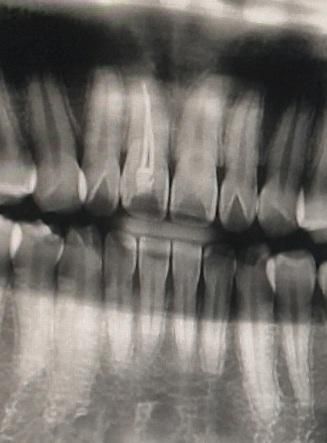

충격으로 인한 신경이 죽은 치아 수명은 어느정도 되나요?

충격으로 인해 앞니의 신경이 죽어 신경치료를 한후 크라운없이 충치도 생기지 않고 8년도넘었고 올해 9년차 동안 치아를 사용했는데 변색은 사진처럼 되어있는 상황입니다.

신경이 죽은 치아는 파절위험이 높다 하여 걱정이 되네요.

• 1번 째 사진